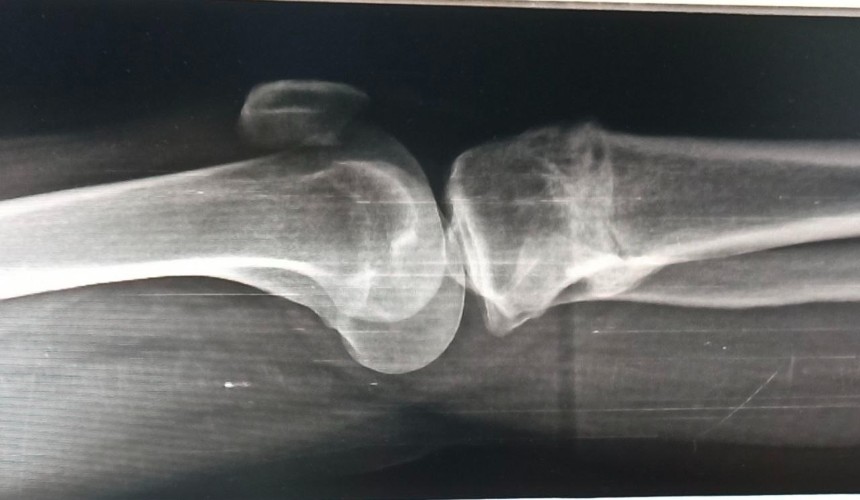

Сибирский государственный медицинский университет приступил к серийному производству нового материала для восстановления костной ткани. Разработку создали совместно с компанией «НПК Синтел», а после внесения вуза в реестр производителей медицинских изделий началось промышленное производство.